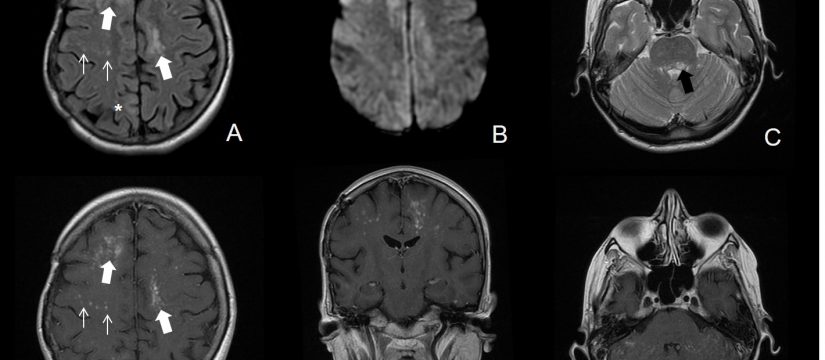

Historia Clínica

Varón de 40 años con esclerosis múltiple remitente-recurrente ya conocida, que consulta por disartria de varios días de evolución.